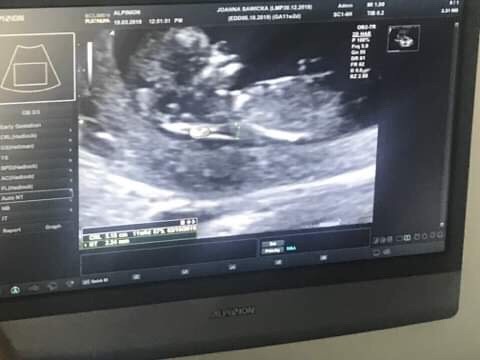

Tak dla pewności przed wyjazdem wskoczyłam dziś na wizytę i maleństwo rośnie pięknie podwoiło swoje rozmiary przez 2 tyg. wiec ma 52mm :) i według USG 11t7d No i lekarz powiedział ze jakby miał coś gdybać to pomiędzy nogami wyglada na chłopaka ale jeszcze nie potwierdza :)

IMG_6928.JPG